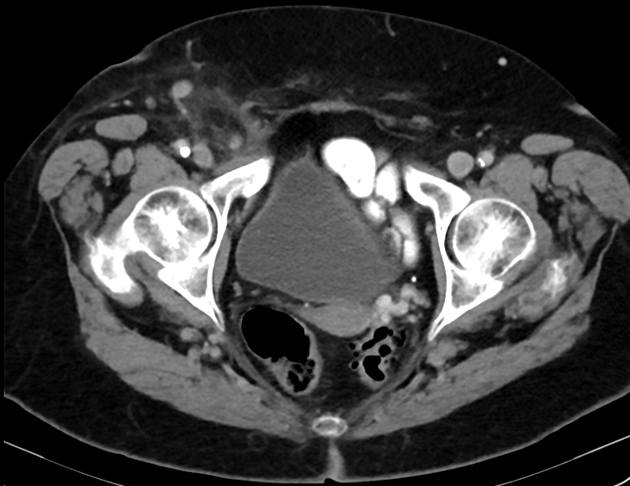

Thoát vị De Garengeot

» Thông tin: Nữ giới – 85 tuổi.

» Lâm sàng: Đau háng phải.